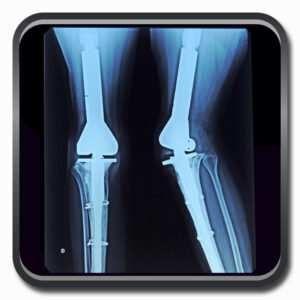

Algumas Cirurgias Complexas realizadas por profissionais da COFIB: